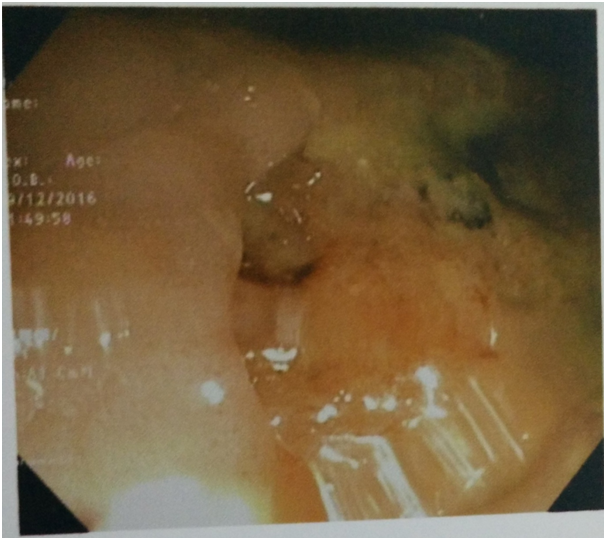

The investigations showed Hb-12.1gm/dl, ESR-45mm 1st hour, total leucocyte count-8700/mm3, differential leukocyte count: neutrophil(63%), lymphocytes(27%), eosinophils(5%), monocytes(4%), and basophils(1%). Biochemical investigations showed Fasting blood glucose-98.0mg/dl, blood urea-30.8mg/dl, serum creatinine-1.1mg/dl, serum bilirubin-0.8mg/dl, AST-34.0 IU/L, ALT-32.3IU/L, Alkaline phosphatase-100.8IU/L. Viral markers for HIV, HBSAg, and HCV was found to be negative. Radiography of Chest showed left sided pleural effusion. Radiography of thoracolumbar spine did not show any abnormality. Fistulo gram delineated the tract which was directed upwards posteromedialy. Fine needle aspiration cytology (FNAC) of right inguinal lymph node showed granular necrotic material with few lymphocytes highly suspicious of tuberculosis. MRI of thoracic spine (T2WI) showed a nodular hyperintense intramedullary lesion at T4 vertebral segment with surrounding hyperintense edema extending from T2to T6 vertebral level (Figure 1). With T1 contrast isointense lesion at D4 vertebral segment showed thick ring enhancement. Colonoscopy also showed a large ulcer in the lower part of rectum suggestive of Tuberculosis (Figure 2). The histology of biopsy material taken from perianal lesion showed caseating necrosis, epithelioid cells with Langhan’s type multinucleated giant cells suggestive of Tuberculosis (Figure 3).

Figure 2 Colonoscopy showing ulcerated lesion present at 3-6cm level over right and posterior walls covering almost half the circumference of the lumen with uneven floor mucosa and multiple punctate ulcers. Surrounding mucosa is rolled out and elevated.

A diagnosis of intramedullary spinal tuberculoma with perianal fistula and tubercular ulcer of lower rectum with left sided tubercular pleural effusion was made. Patient was treated with antitubercular therapy(HRZE+HR) and steroid (prednisolone 60mg for 2 months with gradual tapering over 1 month).His lower limb weakness improved over a period of 2 months. Patient was able to walk without support with recovery of perianal fistula and rectal ulcer.